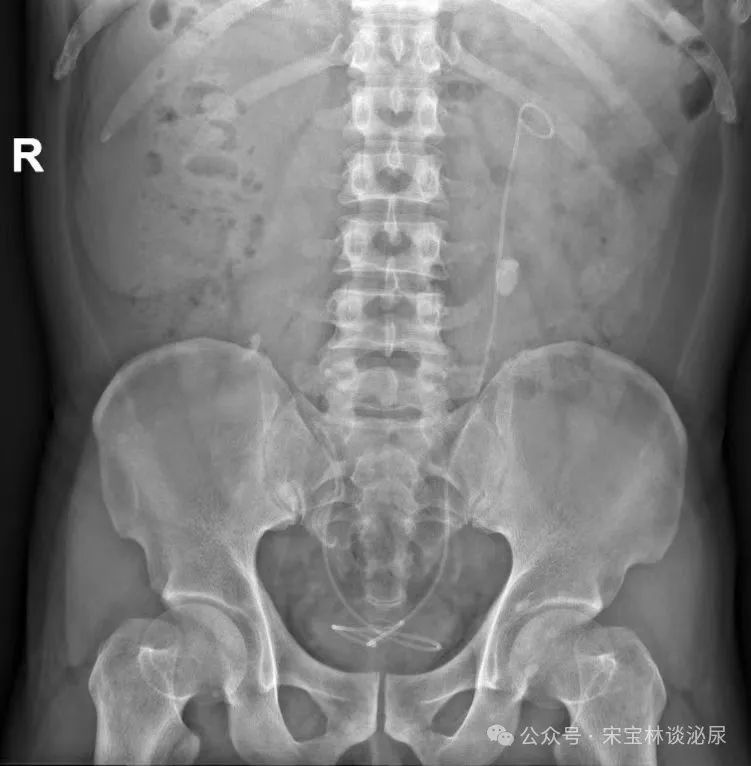

●▽● 左肾积水却在右肾插管 华山医院“网红”医生参与的手术成了医疗事故左肾有病变,手术给右肾插了管江苏盐城的朱女士接受信号新闻(0532-80889431)采访时表示,她被左肾积水困扰多年,在多家医院治疗都没有获得理想的疗效。为求根治,朱女士特意到上海挂了复旦大学附属华山医院泌尿科的专家号,再次确诊“左输尿管狭窄伴左肾积水”。2021年4月19日...